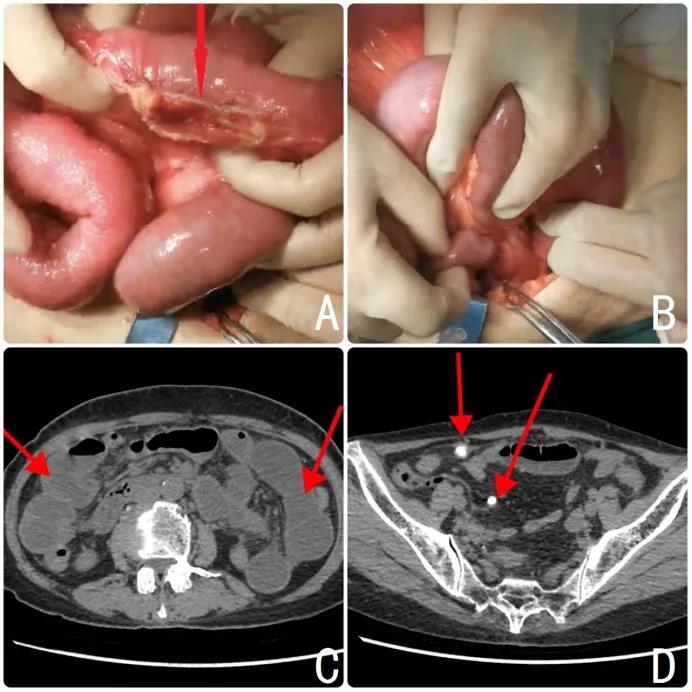

患者,女性,71岁,腹痛、腹胀伴恶心呕吐逐渐加重5天入院,经门诊收入胃肠外科。患者入院后CT增强扫描提示肠梗阻、腹膜钙化灶。

结合影像报告及患者临床体征,与患者家属充分沟通后,行手术治疗。由我院胃肠外科白图克主任医师、韩慧珍副主任医师团队配合,松解腹、盆腔广泛粘连区域,切除呈僵硬状态阑尾时发现系膜内有一质硬重物与阑尾界限不清,予以一同切除,将左上腹粘连梗阻并伴狭窄破裂小肠切除并完成侧侧吻合。

图A.小肠破裂部位。图B.分离广泛粘连系膜。C红色箭头所示梗阻后扩张肠腔。D红色箭头所示为腹腔内多发钙化结节。

术后病理提示小肠破裂、慢性阑尾炎,肠系膜多发淋巴结纤维化、钙化。影像报告、术中所见与病理报告高度一致,相互印证。